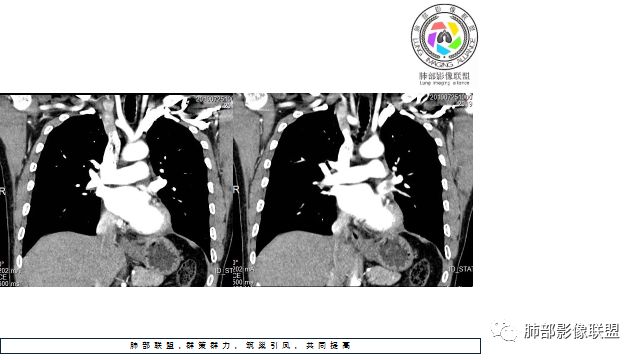

4.病灶内有肺动脉走形,血管局部受压,未见破坏,病灶乏血供,呈血管包埋或血管造影征;侵袭性力强及破坏力弱、血管漂浮都符合SCLC,所以鳞癌的可能性也不大。

5.左肺门块影或淋巴结肿大,竭力挤兑肺门血管结构,呈冰冻肺门;有时候SCLC可以单独呈现冰冻肺门,而没有没有冰冻纵隔。

50岁男性,左肺门肿块沿支气管生长,左肺上叶支气管狭窄,下叶支气管闭塞,左肺动脉近段分支包绕、受压变形,增强后不均匀强化,边缘深分叶,蟹足样生长,考虑恶性肿瘤,以小细胞肺癌可能

中年男性,病史10个月,咳嗽、咳痰,有血痰,1月来经抗炎等治疗无效,并出现气喘、左胸痛。CT见左肺门肿块影,边缘清,见分叶,支持恶性肿瘤。病灶堵塞左下叶支气管,但左下肺无阻塞性肺不张,阻塞性炎症不明显,提示病变沿支气管粘膜下蔓延生长为主;增强见左下肺动脉被病变包绕,血管破坏不明显,左肺下静脉被推移,提示其破坏力不强;病灶外缘间条片状影;NSE升高。考虑小细胞肺癌。可支气管镜检查明确。